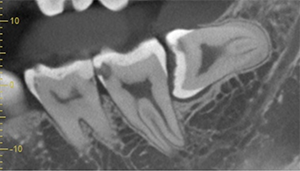

右下の親知らずが疼く症例

- 抜歯前写真(レントゲン)

- 抜去歯の写真(CT画像)

| 年齢 | 30代・女性 |

|---|---|

| 主訴 | 右下親知らずが疼く |

| 親知らずの生え方 | 横向きに生えている |

| 抜歯時間 | 40分 |

| 費用 | 約8,000円(保険診療、CT代含む) |

| 抜歯内容 | 右下の親知らずは横向きに生えて埋まっているため、麻酔をし親知らずの奥に切開を入れて歯ぐきを開き、歯を囲んでいる骨を削り歯の頭部分を割って出してから、残った根の部分を取り出して抜歯は終了しました。 歯ぐきを切った部分は糸で縫っています。このケースでは根の先端が神経に近く麻痺のリスクがありましたが事前にCTを撮影し、神経との位置関係を確認していたため、麻痺が残ることはありませんでした。 約1週間後に糸取りを行い、その際も多少の痛みや腫れはありましたが後日その痛みも無くなりました。 |